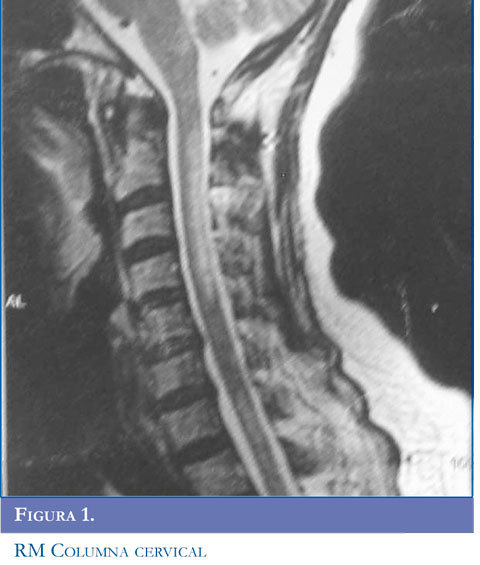

Hallazgos radiológicos

En la NMO, las lesiones de la médula espinal tienden a extenderse sobre tres o más segmentos vertebrales (Figuras 1 y 2 ). Se puede encontrar una apariencia de normalidad o menos lesiones, muy temprano en las recaídas o en la etapa atrófica residual (22). Las lesiones se observan como hiperinten-sidades en T2 e hipointensidades en T1 que suelen ocupar la mayor parte del área de sección transversal del segmento afectado y se asocian con inflamación y captación de gadolinio (23).